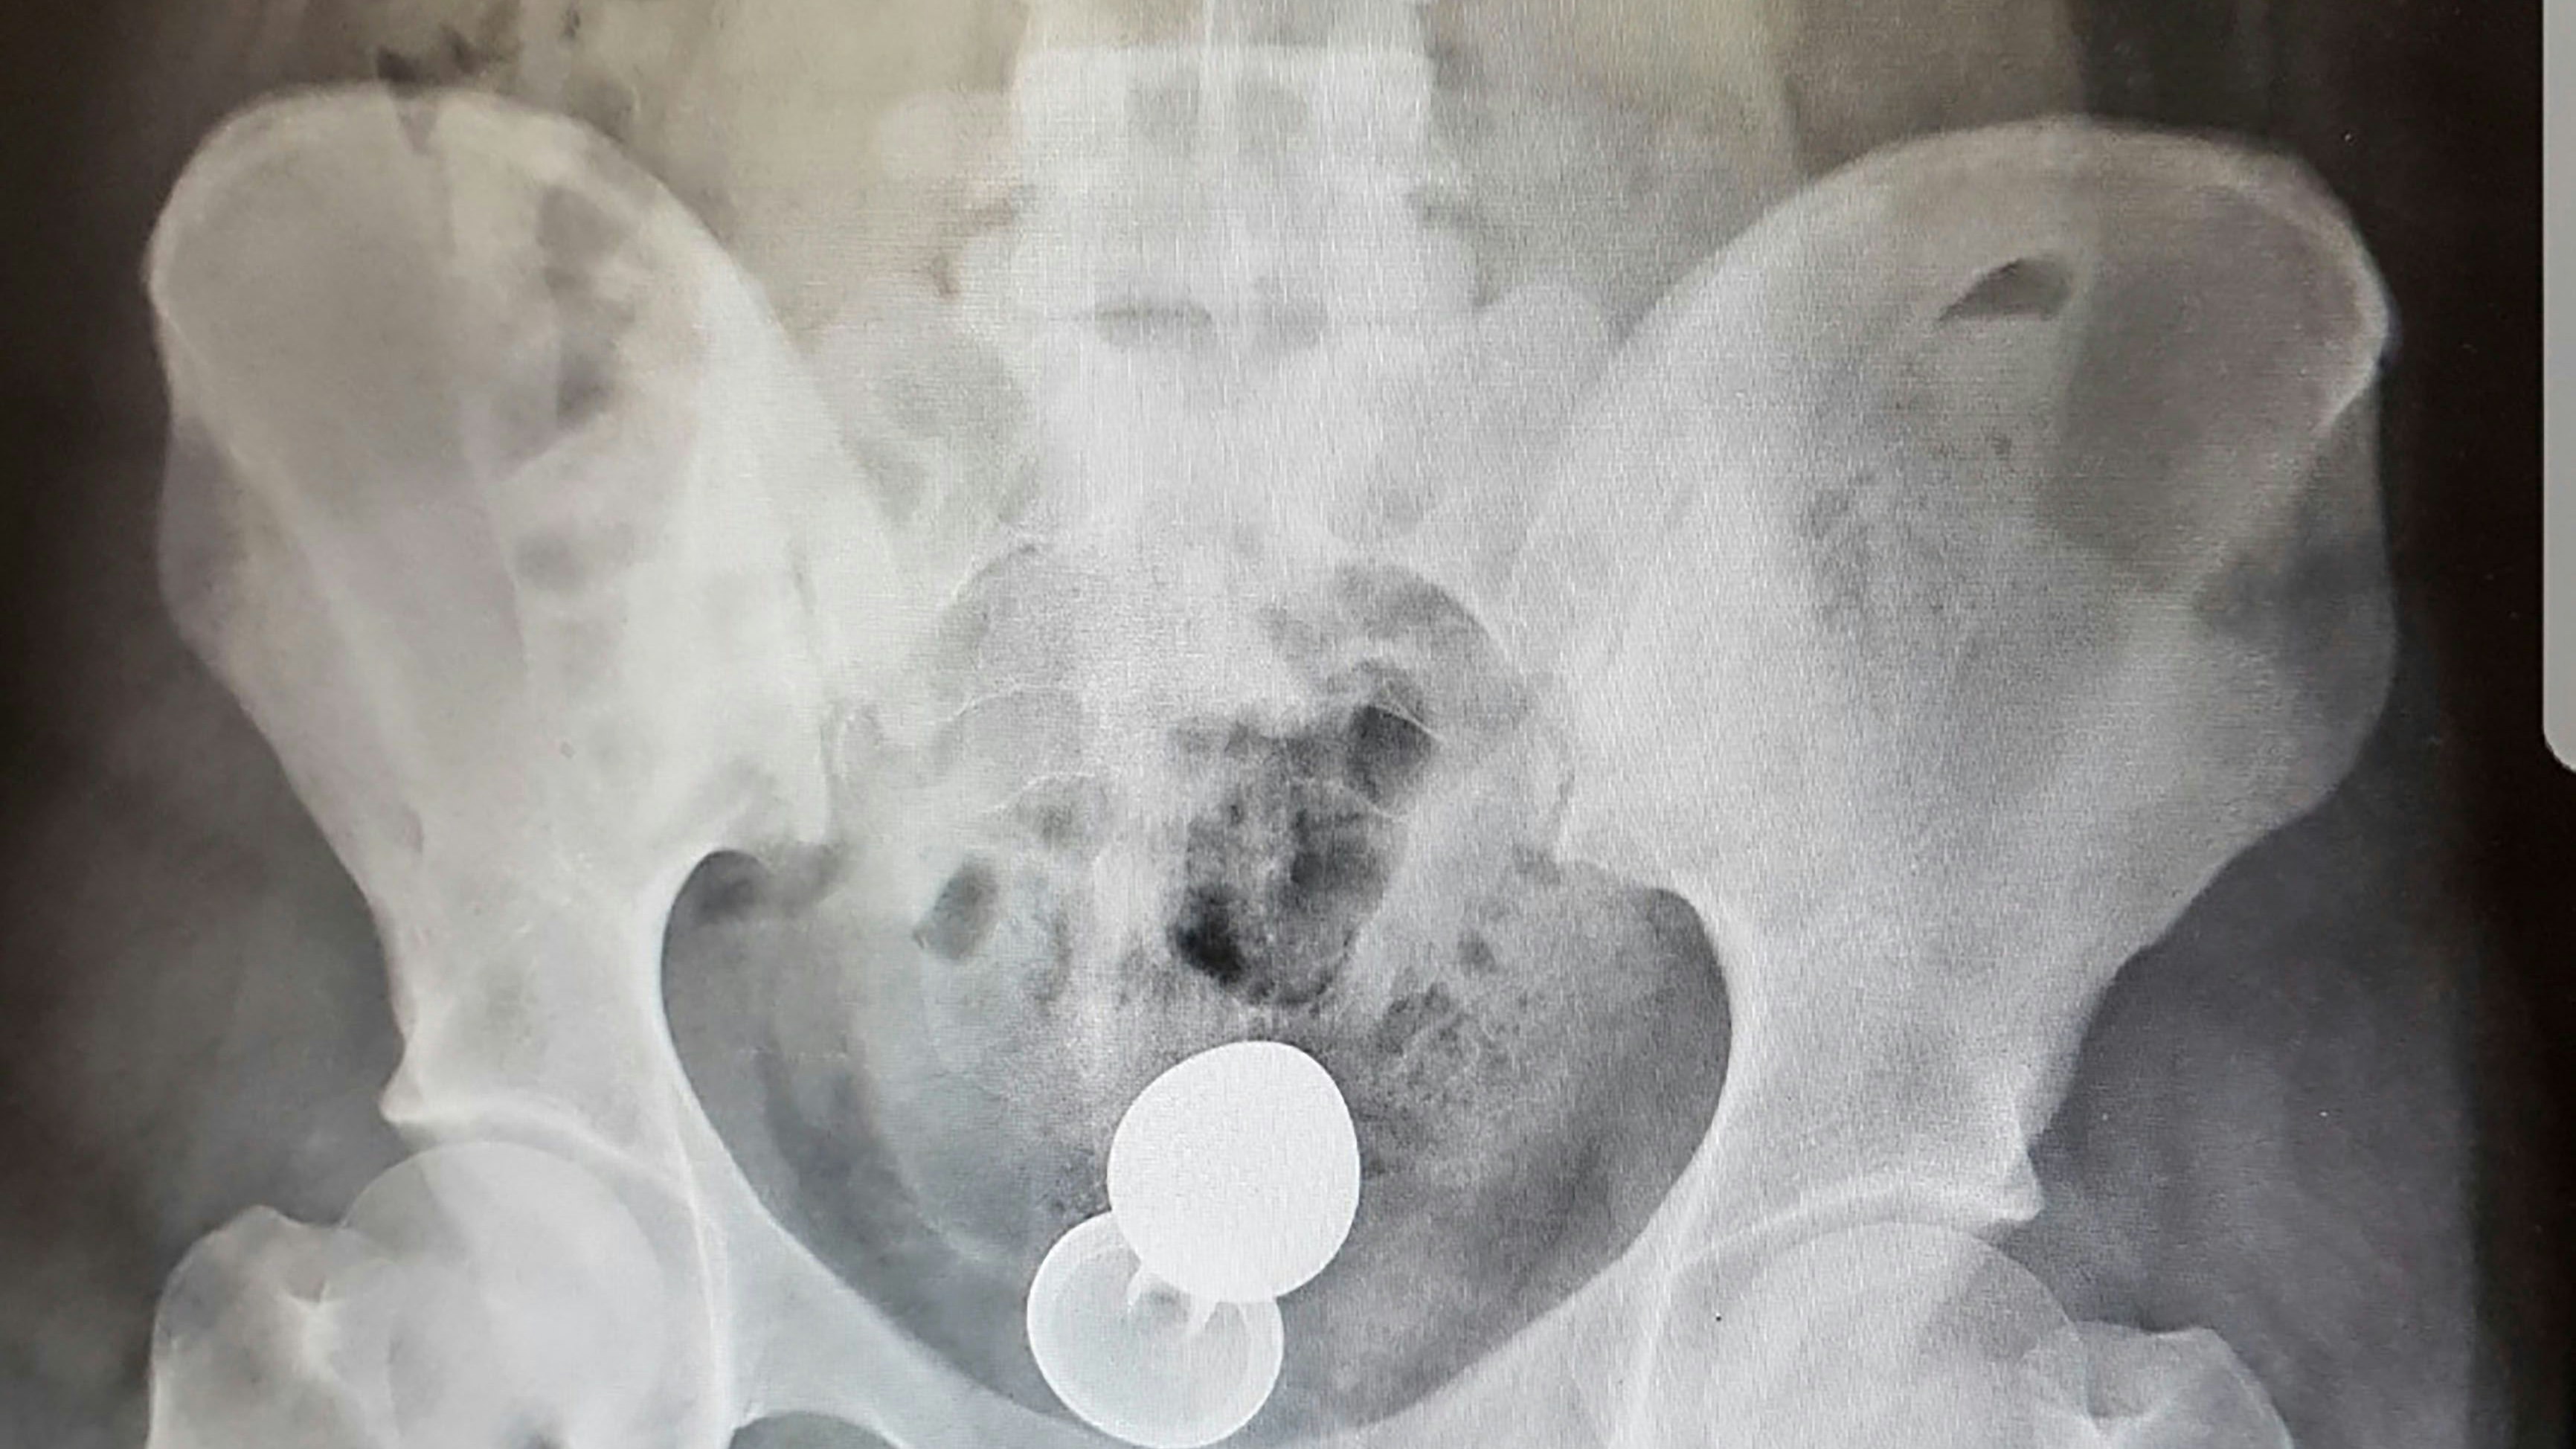

Ein 31-jähriger Inder ist Ende Juli in einer äußerst prekären Lage in das Vietduc-Uniklinikum in Hanoi, Vietnam, auf dem OP-Tisch gelandet. Der Mann war mit extremen Bauchschmerzen aufgenommen worden, doch bei ihrer Untersuchung machten die Ärzte einen schockierenden Fund. Wie die "Times of India" berichtet, leuchtete auf dem Röntgenbild ein komplettes Tier-Skelett im Bauchraum des Mannes auf!

Der 31-Jährige hatte sich offenbar einen lebenden Aal anal eingeführt. Der Fisch hatte in Panik die Flucht durch das Rektum nach vorne angetreten und sich dann mit seinen scharfen Zähnen durch die Darmwände gebissen, lag nun mitten in der Bauchhöhle.

Die Ärzte wollten das verirrte Tier eigentlich auf dem selben Weg entfernen, auf dem es in den Körper gelangt war. Doch war der Darmausgang durch eine Limette blockiert! Sofort wurde deshalb eine Notoperation durchgeführt.

Dabei konnten sowohl der rund 63 Zentimeter lange Anal-Aal sowie die Zitrusfrucht erfolgreich entfernt werden. Zur Sicherheit wurde noch nach weiteren Fremdkörpern gesucht. Dazu wurde ein künstlicher Darmausgang gelegt, damit es nicht zu einer weiteren Infektion der Bisswunde und dem dahinterliegenden Bauchraum kommt.